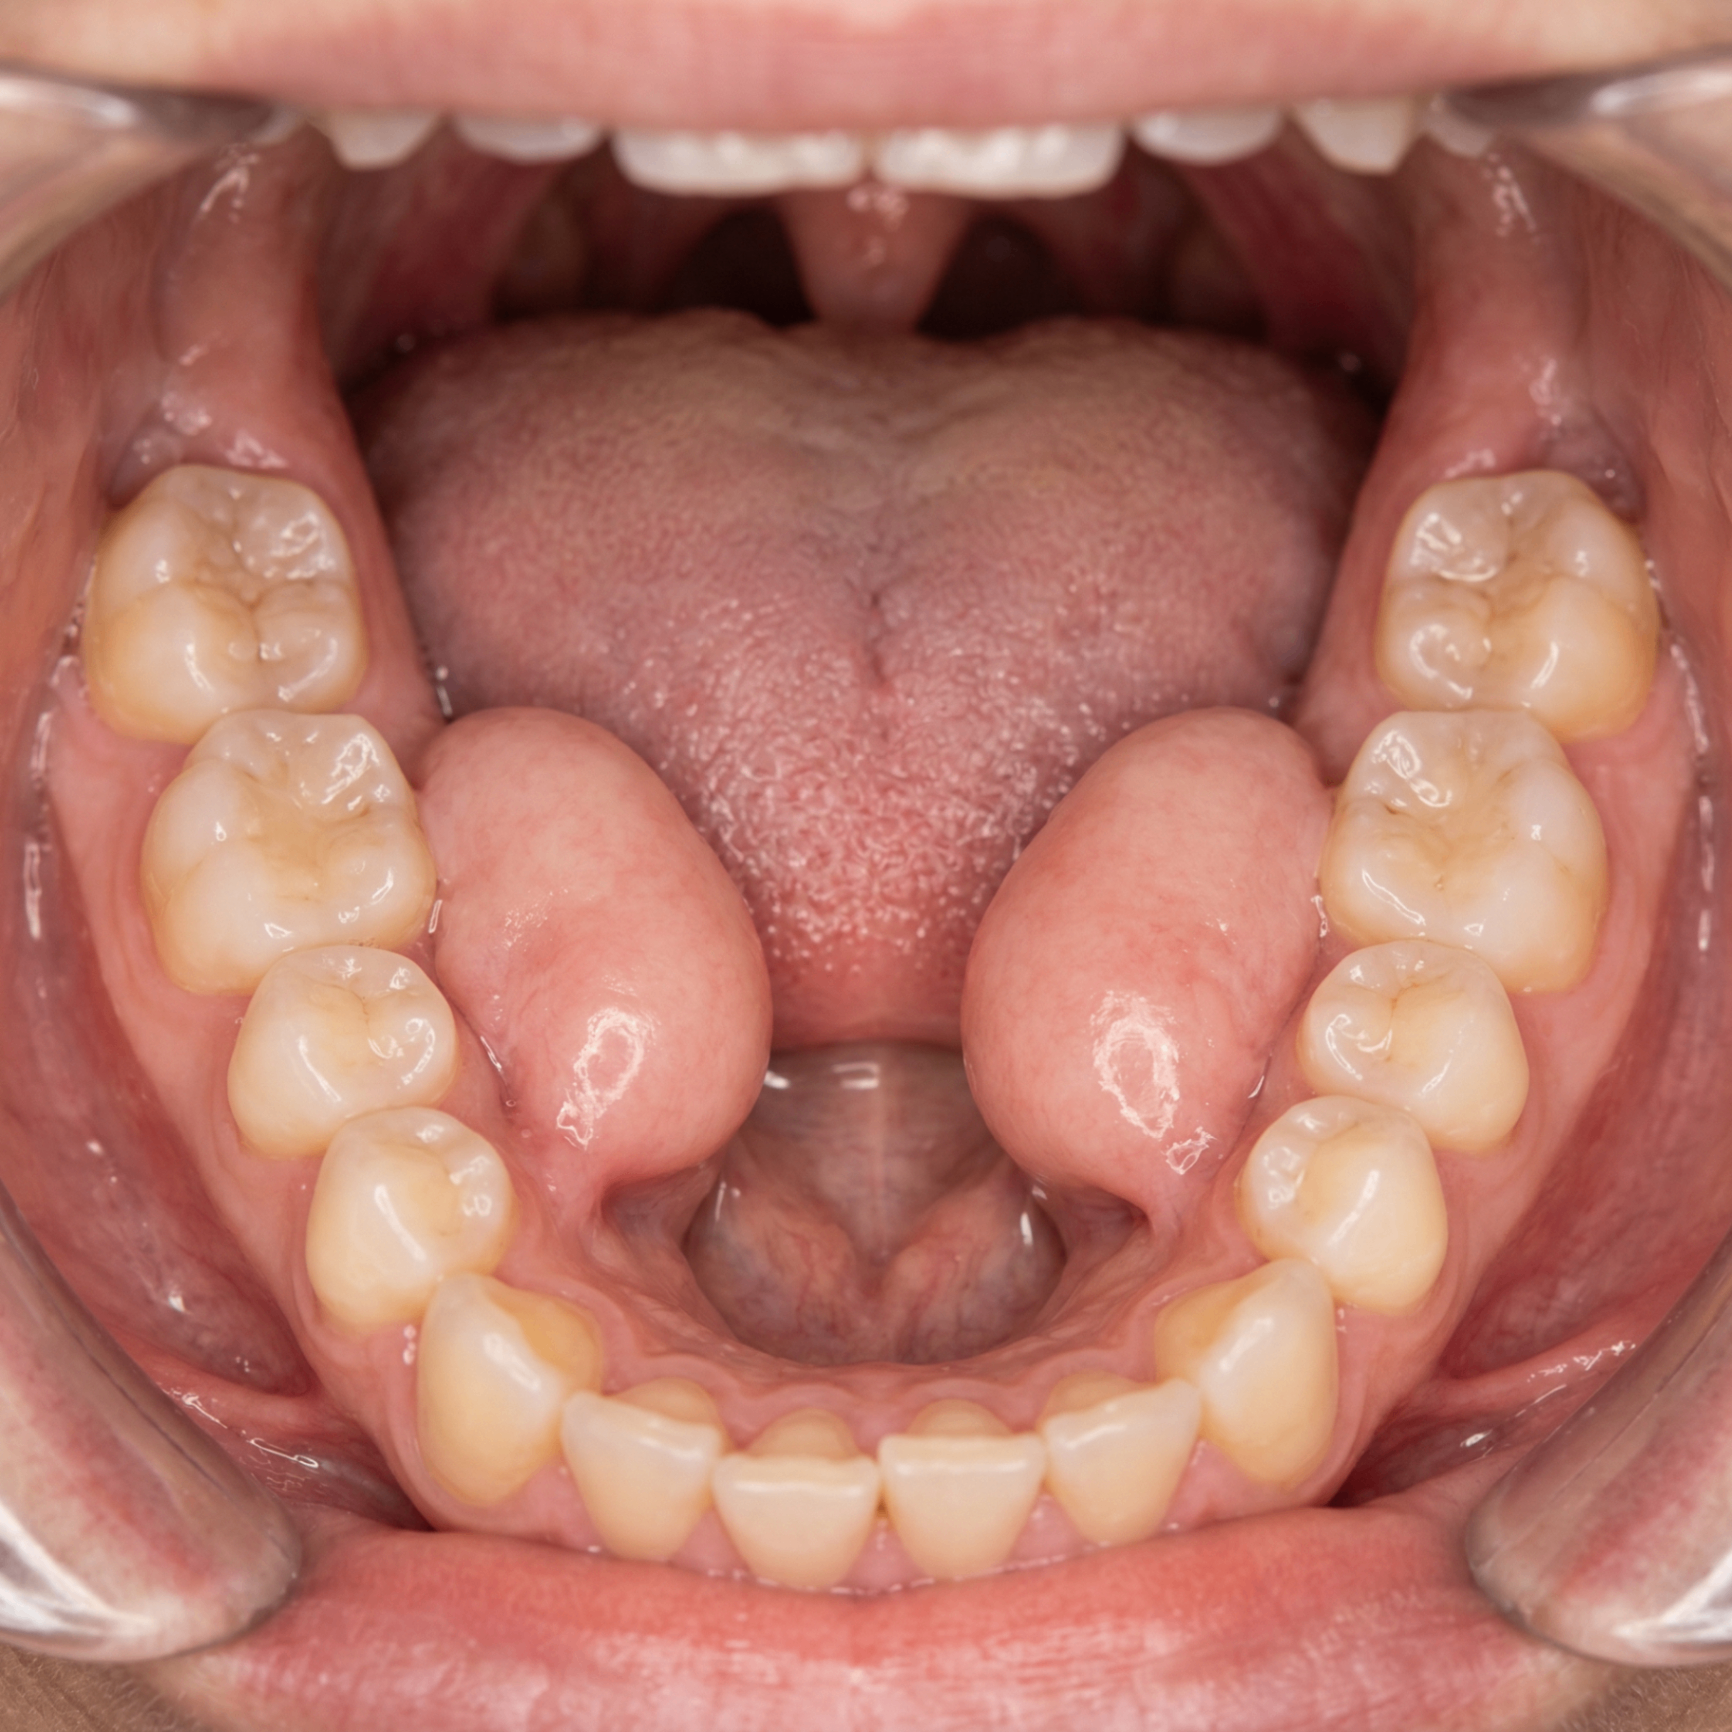

Torus Mandibularis

Bony growths along the inner surface of the lower jaw, usually on both sides near the premolar teeth. They can grow as single or multiple nodules.